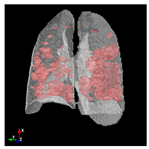

In Table 6, a comparison of the ground truth and prediction results of each model is presented in 2D, along with the 3D projection of each model. The visual analysis of the predictions provides additional insights into the performance of each model. The visualizations demonstrate that Attention UNet captures the intricate details of the lung construction more accurately, resulting in more precise segmentation of the infected areas compared to other models.

Table 6.

Comparison of ground truth and model prediction results using UNet, LinkNet, Attention UNet, UNet 3+, and TransUNet.

Attention UNet stands out due to its sophisticated attention mechanisms that allow it to focus on relevant regions and features within the lung structures. This characteristic enhances its ability to capture intricate details specific to COVID-19-affected lungs. The attention mechanisms contribute to Attention UNet’s impressive IoU score of 85.36% and dice score of 91.49%, showcasing its potential to provide accurate and finely detailed segmentations. The results suggest that its trait of dynamically assigning different weights to regions, based on their contextual importance, is instrumental in achieving precise and meaningful segmentations in complex medical images.